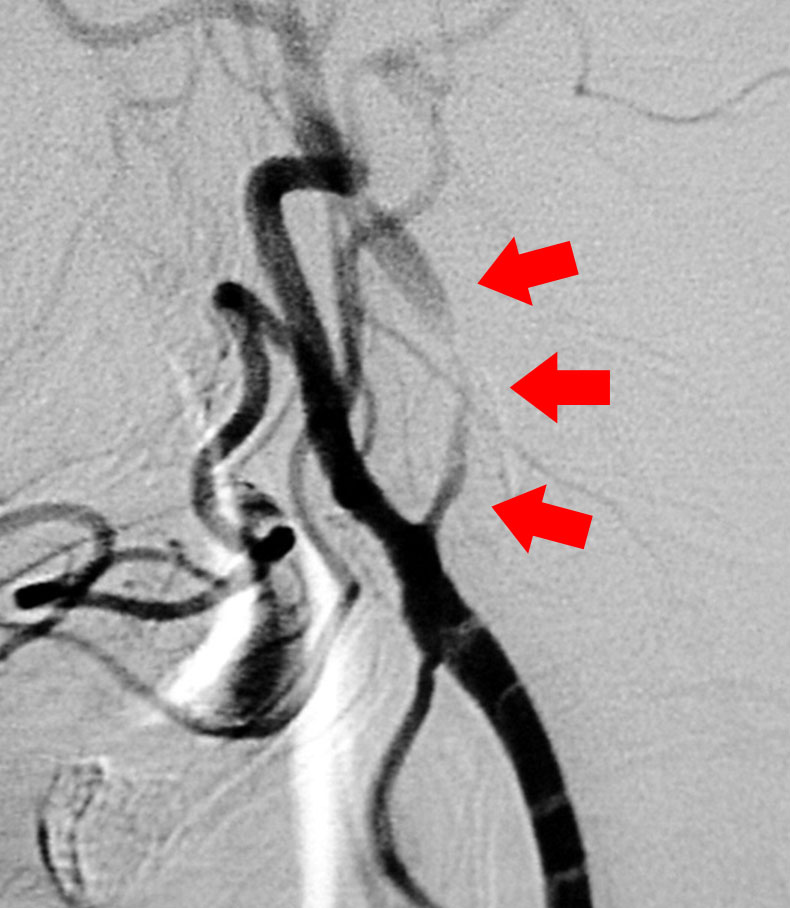

術中脳血管撮影

治療困難な大型動脈瘤や深部にある動脈瘤では顕微鏡観察だけでは完全なクリッピングができているのか、或いは動脈瘤の親血管が狭くなっていないかといった検討が十分にできないことがあります。そこで当科では術中血管撮影を行い、完全なクリッピングと、親血管の血流が保たれていることを手術中に確認し、手術の確実性、安全性を向上させています。

当科では放射線治療班と症例検討を行い、個々の患者さんに最も適切は治療を提供しています。 脳動静脈奇形の手術では、術中脳血管撮影を常に行い、全摘出を確認しています。また場合によっては脳動脈瘤手術同様に電気生理学的モニタリングも併用し、確実、安全な手術を行っています(図7、8)。